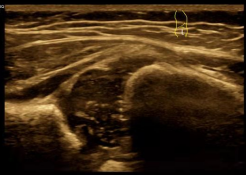

2、超声在关节方面的应用:超声检查可应用于全身各个关节,包括肩关节、肘关节、腕关节及手关节、髋关节、膝关节、踝关节和发育性髋关节发育不良。适用于关节肿胀、疼痛,活动运动,关节弹响等,判断关节周围肌肉、肌腱、韧带病变(如肌腱或韧带撕裂、肌腱炎性病变等),关节周围软组织病变(如占位性病变等)。超声探查关节积液是非常敏感和可靠的方法,不论是在关节线水平还是在关节隐窝和关节旁滑囊都能获得可获得满意的超声图像。并且可以诊断和鉴别诊断软组织牵涉性疼痛和关节旁病变导致的疼痛,在评估关节活动功能障碍与其周围肌腱、韧带等软组织结构生物力学性能等方面有重要作用。

图2. 髋关节发育不良